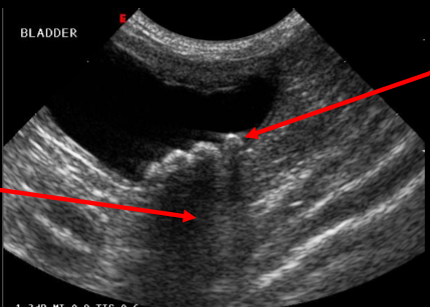

Q

Label this bladder